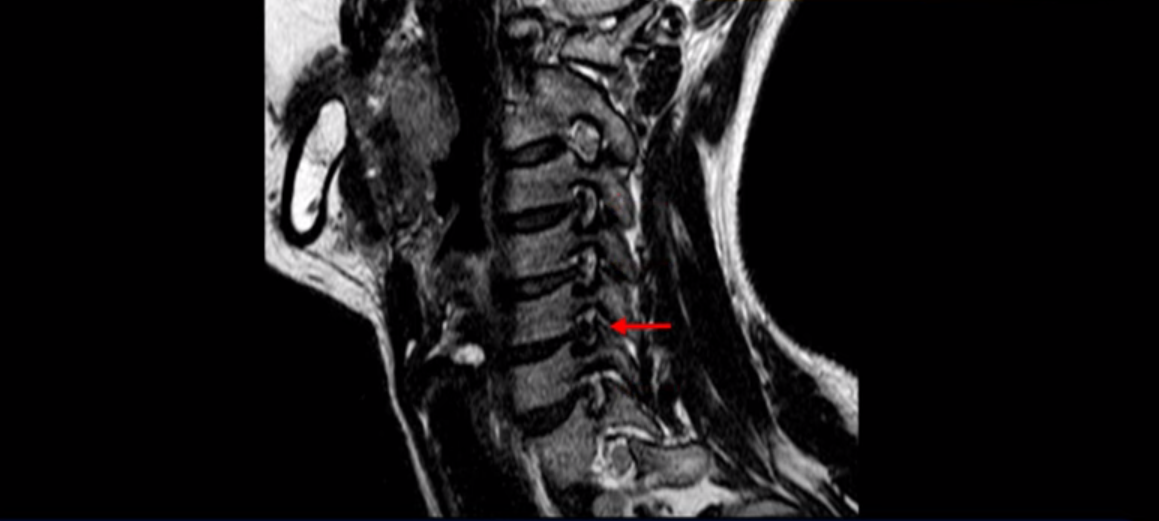

우선 이분 MRI를 보기 전에 이분 증상에 대해 말씀 드리면 오른쪽 팔저림과 방사통 및 어깨 통증이 있습니다. MRI를 보면 4번 5번에 디스크 파열이 보입니다.

그런데 이분 목을 보시면 여러 마디의 뼈가 퇴행이 진행되어 있습니다. 뼈가 깍두기처럼 각지고 예뻐야 하는데 끝이 조금씩 변형되어 뾰족하게 자라고 있습니다.

이런 게 협착을 일으킵니다. 그래서 우선 오른쪽 신경구멍 즉 추간공을 살펴보면 맨 위의 한마디를 빼고는 다 좁아져 있습니다.

특히 5번 6번 구멍이 가장 좁습니다. 이걸 협착이라고 합니다.

목 치료가 쉽다고 하는 것은 이러한 근육치료가 허리에 비해 훨씬 더 쉬운 겁니다. 목 근육이 허리 근육에 비해 훨씬 구조도 단순하고 치료하기도 쉽습니다. 또 목은 머리만 받치고 있기 때문에 허리에 비해 부담을 적게 받습니다. 그래서 치료하기가 훨씬 더 쉽고 빠른 겁니다. 이분 목 X-RAY를 보면 일자목이면서 커브도 매우 좋지 않습니다. 이런 일자목, 거북목 상태에서는 목 주변 근육이 만성적으로 굳어있고 뭉쳐 있을 가능성이 매우 높고 그러니까 만성적인 목 통증이 있는 겁니다. 이런 뭉치고 굳어있는 근육이 목뼈를 심하게 잡아당기면 신경 자극 증상이나 신경 눌림 증상이 생기기 쉽습니다.